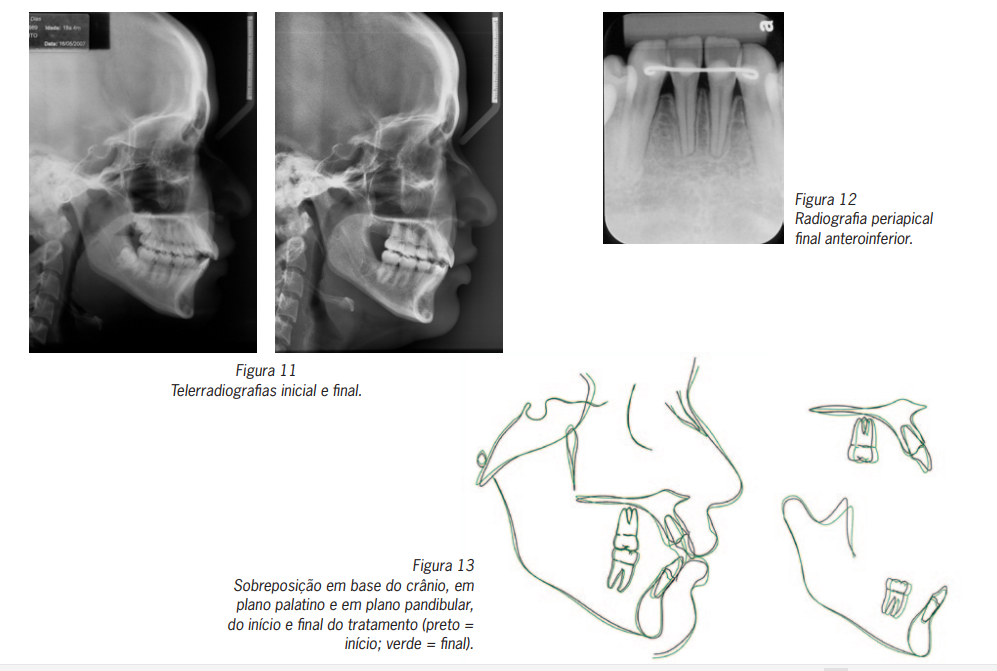

Comparando-se as imagens das telerradiografias inicial e final, observou-se a lingualização dos incisivos superiores e inferiores, melhorando o perfil tegumentar da paciente (Figuras 11).

Pela radiografia periapical dos dentes anteroinferiores, pôde-se verificar o paralelismo radicular dos incisivos (Figura 12).

Como a jovem não se encontrava mais em fase de crescimento (apresentava-se com 18 anos de idade ao início do tratamento), as alterações promovidas pelo tratamento realizado foram essencialmente dentoalveolares, uma vez que pacientes adultos não apresentam crescimento significativo, durante o tratamento ortodôntico, que possa promover alterações nos componentes esqueléticos da maxila e mandíbula, ou mesmo nos componentes verticais12-14 (Figura 13).

Normalmente, extrações dentárias favorecem a inclinação e a retração dos incisivos superiores15. Com relação às alterações dentoalveolares promovidas neste caso, verificou-se uma lingualização dos incisivos superiores, acompanhada de

retração e suave extrusão, como demonstram as alterações das variáveis IS.NA, IS-NA e IS-PP, respectivamente. A alteração

mais evidente foi a lingualização dos incisivos superiores, esperada e necessária para a correção da sobressaliência (overjet)

causada pela protrusão inicial destes dentes, e para a correção do selamento labial, melhorando a estética facial da paciente.